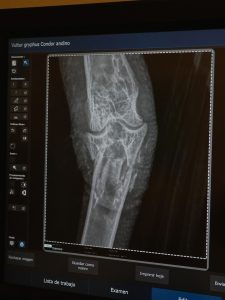

La historia comenzó en la provincia de Chubut, donde el ejemplar fue hallado tras caer accidentalmente en una trampa para pumas. El dispositivos le provocó al condor una fractura grave en una de sus patas.

Al ingresar al Hospital Veterinario de la Fundación Temaikèn, el equipo médico realizó una cirugía de alta complejidad para intentar salvar la extremidad. Sin embargo, debido a la severidad de la lesión, la recuperación total del miembro no fue posible.

Ante la imposibilidad de que el cóndor pudiera desplazarse por sus propios medios, cuidadores y veterinarios asumieron un desafío sin precedentes: diseñar y adaptar una prótesis funcional.